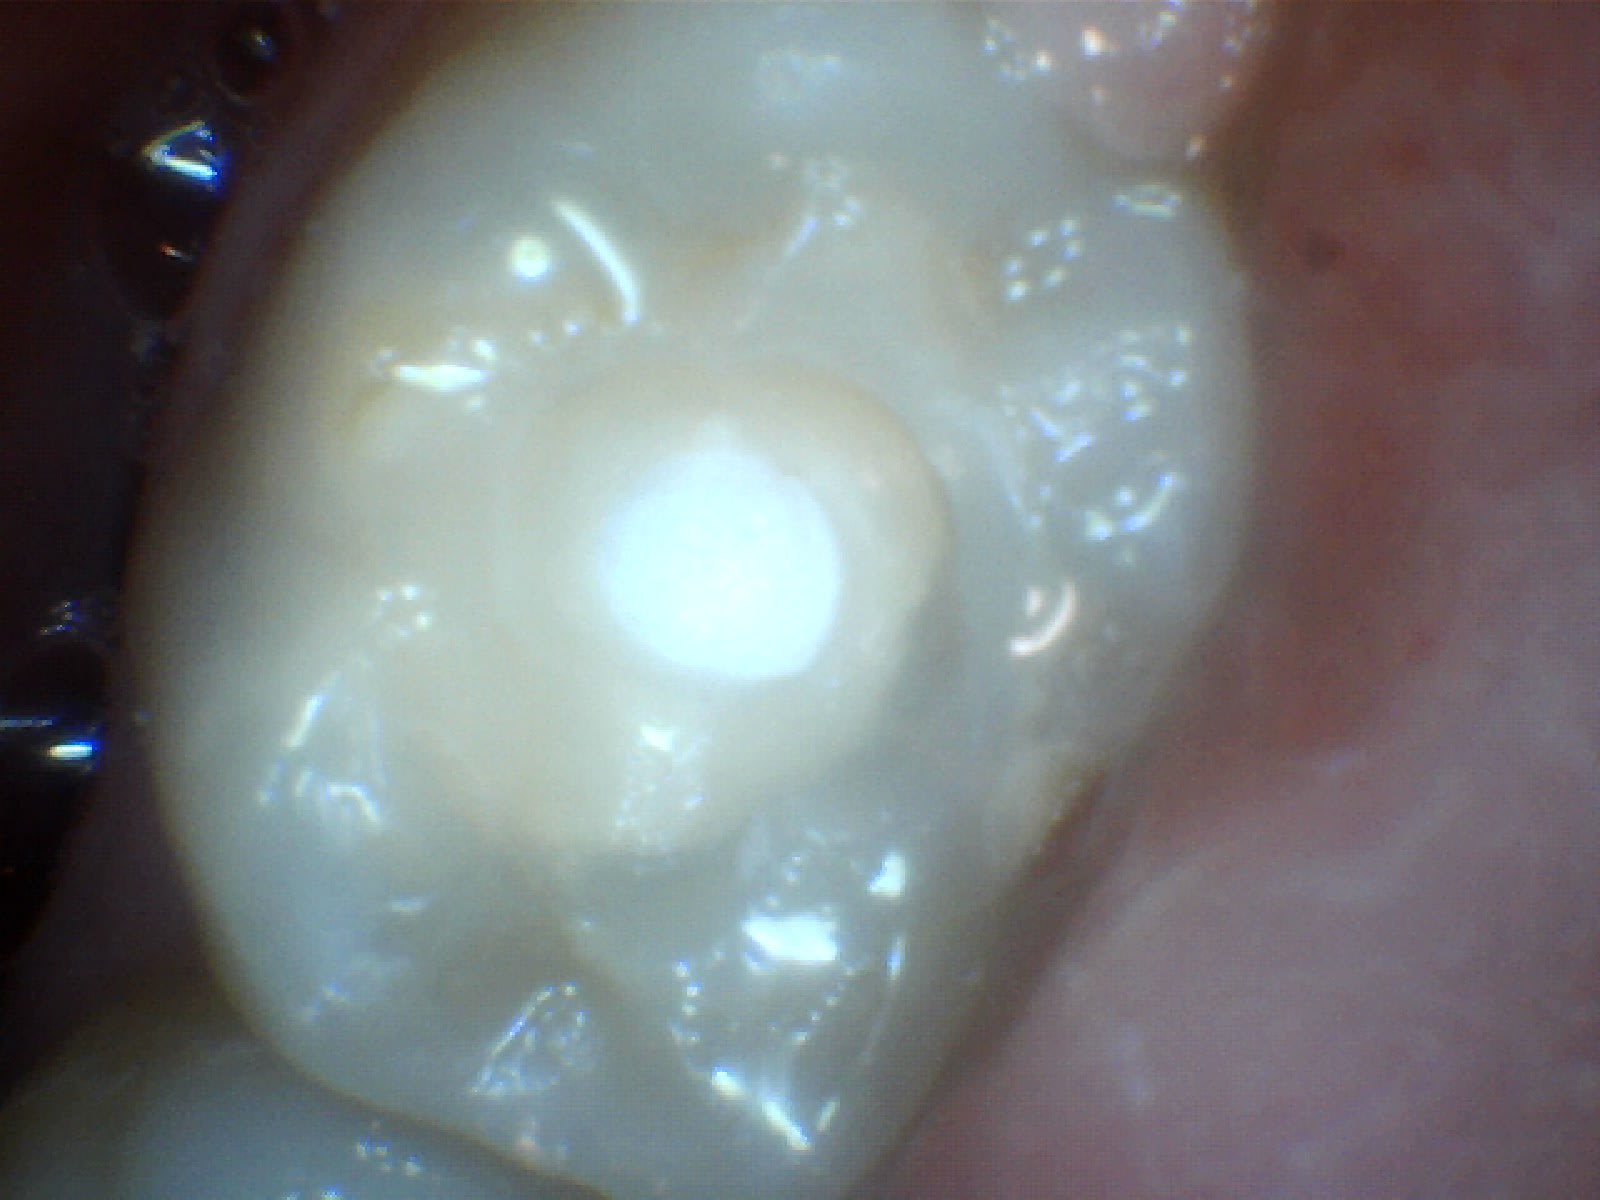

du coup j'ai revu le patient

j'ai démonté le soin, j'ai vu le fond de cavité que j'ai deposé mais pas de carie dessous visible

j'ai remis de la résine sans fond de cavité,

J'ai prévenu le patient des risques de sensibilité post op qui pouvaient venir à cause de fait que j'ai déposé le fond de cavité. Et que s'il y avait des sensibilités, il faudrait dévitaliser la dent.

Perso j aurais jamais pensé voir un truc aussi propre... j' avais vraiment tort. Désolé...

Je pensais trouver une dentine noire ébène... Ramollie mais assez dure... De la carie a progression très lente.

Du coup c'était quoi le fond de cav ?? Ça sentait l eugenol ??